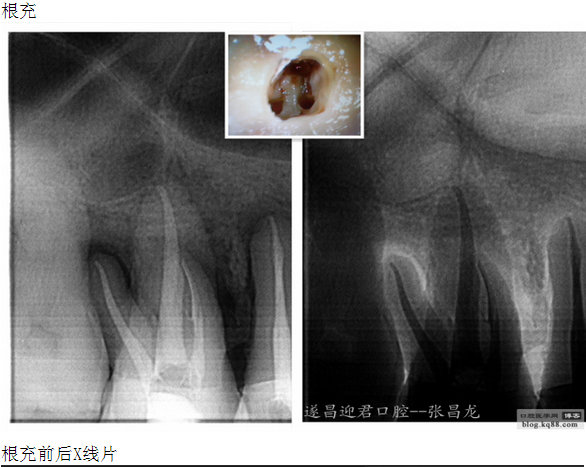

下面是我最近的一個(gè)患者,患者14,15,16均因楔狀缺損導(dǎo)致牙髓壞死,根管治療期間,16的近中頰根發(fā)生了斷針。

每個(gè)牙科醫(yī)生都不愿碰到器械分離,但常在河邊走,哪有不濕鞋的,我想大部分醫(yī)生根管治療中都發(fā)生過(guò)器械分離吧。在此就不在累贅那些造成根管器械分離的原因,醫(yī)生們也都知道那些。遇到器械分離莫慌,我們還是有挽救的余地。由于醫(yī)生的技術(shù)原因,設(shè)備原因,不是每個(gè)斷針都能取出來(lái)的。與對(duì)一部分?jǐn)噌樜覀兛梢試L試建立旁路通道,斷針與根管壁之間的間隙慢慢通入到工作長(zhǎng)度,然后常規(guī)根管治療。